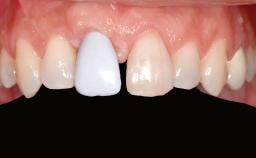

Shell Technique for Horizontal and Vertical Maxillary Bone Augmentation in a Partially Edentulous Patient with Aggressive Periodontal Disease